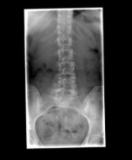

Active axial spondyloarthritis with advanced structural lesions